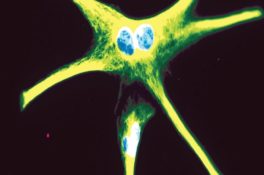

Pinto-Benito, D., Paradela-Leal, C., Ganchala, D., de Castro-Molina, P., & Arevalo, M.-A. (2022). IGF-1 regulates astrocytic phagocytosis and inflammation through the p110α isoform of PI3K in a sex-specific manner. Glia, 70( 6), 1153– 1169. https://doi.org/10.1002/glia.24163

Pinto-Benito, D., Paradela-Leal, C., Ganchala, D., de Castro-Molina, P., & Arevalo, M.-A. (2022). IGF-1 regulates astrocytic phagocytosis and inflammation through the p110α isoform of PI3K in a sex-specific manner. Glia, 70( 6), 1153– 1169. https://doi.org/10.1002/glia.24163

Cover Illustration: Confocal microscopy image of primary culture of female astrocytes, stimulated with bacterial lipopolysaccharide (LPS) and treated with insulin-like growth factor (IGF-1). The image shows the reactive morphology of the cytoskeleton (glial fibrillary acidic protein-green), induced by LPS. IGF-1 cannot reduce reactivity in female astrocytes, only in male astrocytes, indicating that male and female astrocytes show different inflammatory outcomes with LPS administration and IGF-1 treatment. (See Pinto-Benito, D., et al.